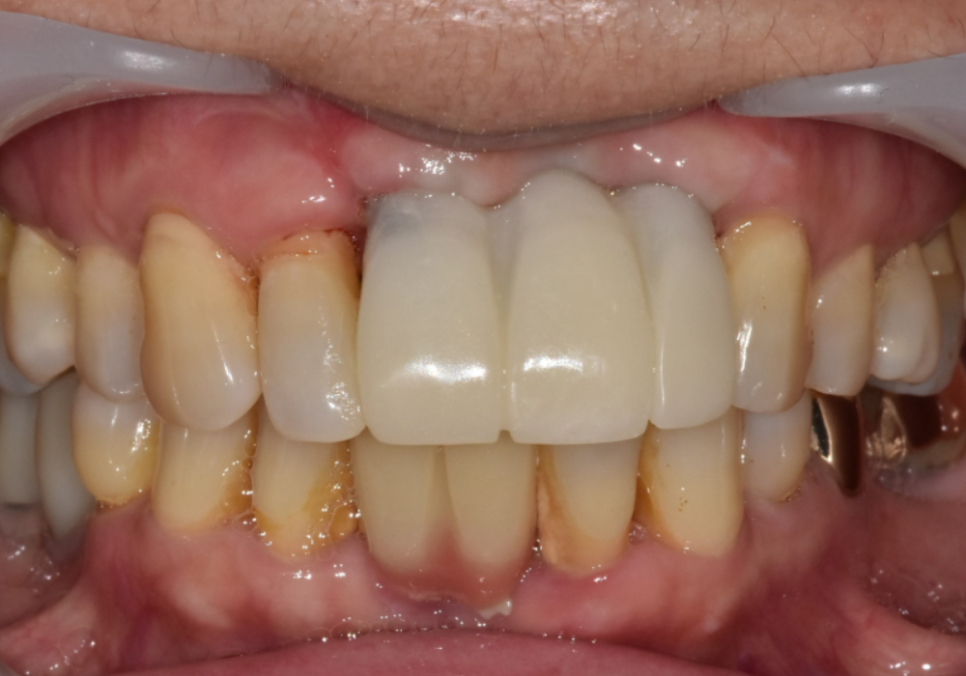

드디어 완성된 최종 보철물.

230826(전) 240619(후)

최종 보철은 형태와

색이 자연스럽게 정리됐고,

앞니가 도드라져 보이던 느낌도

부드럽게 잡혔습니다.